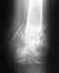

дтп на мотоцикле.сначала поставили два неполных диагноза (сначала просто ушиб, а потом в другой больнице увидели перелом надколенника поперечный без смещения). лечение = месяц в гипсе (+пунктирование). Потом в платной клинике после КТ и МРТ диагноз уже включал отрывные переломы берцовой кости, разрыв пкс и зкс и еще несколько подробностей. Суть = осколки надколенника и берцовой кости + разрыв пкс зкс и повреждение мениска. Назначили пластику пкс, зкс и артроскопию. На август.Делают ли в УНИИТО такие операции и на каком основании (только платно, оплата материалов, полностью за счет федерального бюджета на основании обяз.страхования) а также в какие примерные сроки можно сделать операцию.